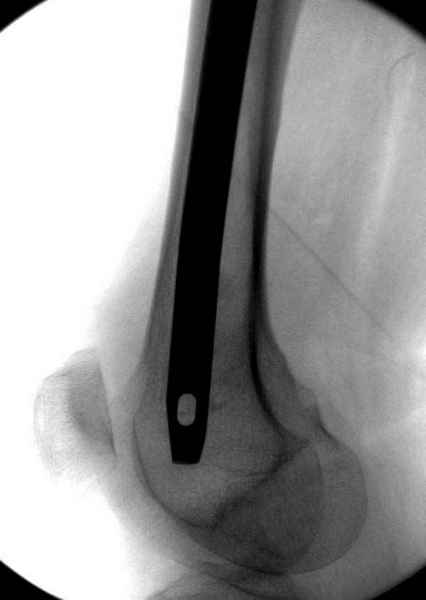

На второй день после выписки упал дома. Снимки приложены. Коллеги рекомендуют удаление шурупа и вытяжение. Что делать?

Правильно, ситуация изменилась, как говорят у нас теперь "different animal", надо решать проблему подвертельного перелома. При наличии различных вариантов фиксаторов, включая Страйкер Гамма 3, мы выбрали DePuy Antegrade Trachanteric Nail из-за многовариантности проксимальной фиксации и двойного изгиба. Вводится через вертел под 8 градусным углом, и есть достаточный передний диафизарный изгиб, предупреждающий пенетрацию дистального переднего кортекса.